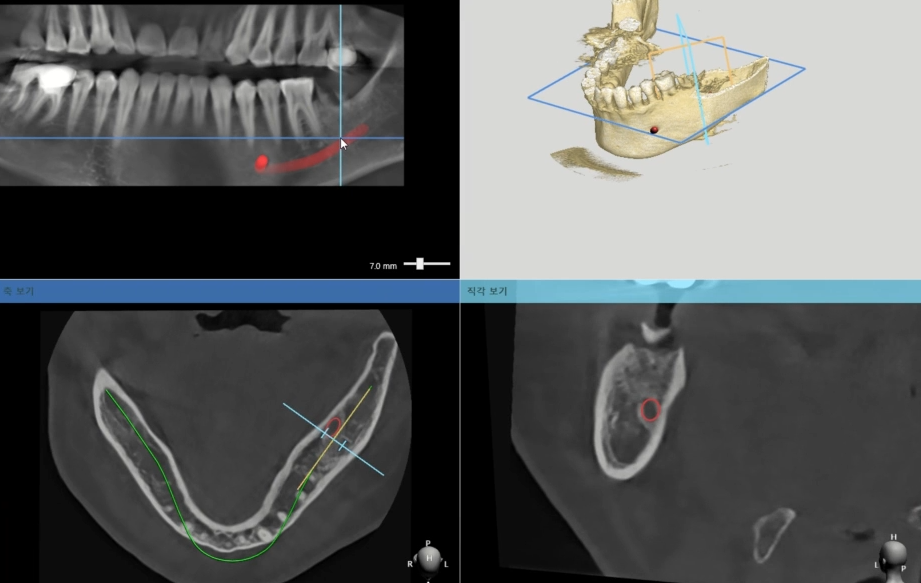

✔ 정밀한 디지털 치료

최신 3D 진단 장비와 컴퓨터 가이드

수술을 통해 정밀한 치료가 가능합니다.

CT 촬영으로 상악동의 위치, 상악골의

상태, 신경의 위치, 혈관의 분포를

정확히 파악하여 안전한 수술을

진행할 수 있습니다.

CT 촬영과 구강 스캔을 통해 3차원적인

상악 구조를 정확하게 파악합니다.

상악골의 두께, 높이, 밀도와 함께

상악동까지의 거리를 측정하여 임플란트

크기와 위치를 결정합니다.

✔ 컴퓨터 시뮬레이션

기존 치아들의 발치 순서와 임플란트의

개수, 위치, 각도를 컴퓨터 시뮬레이션으로

정밀하게 계획합니다.

✔ 안전 계획 수립

수술 가이드 제작을 위한 모의수술을

컴퓨터상에서 진행합니다.

발치와 동시 임플란트 식립이 가능한지

평가하고 상악동 손상이나 신경, 혈관

손상 위험을 최소화하는 안전한 식립

경로를 찾아냅니다.